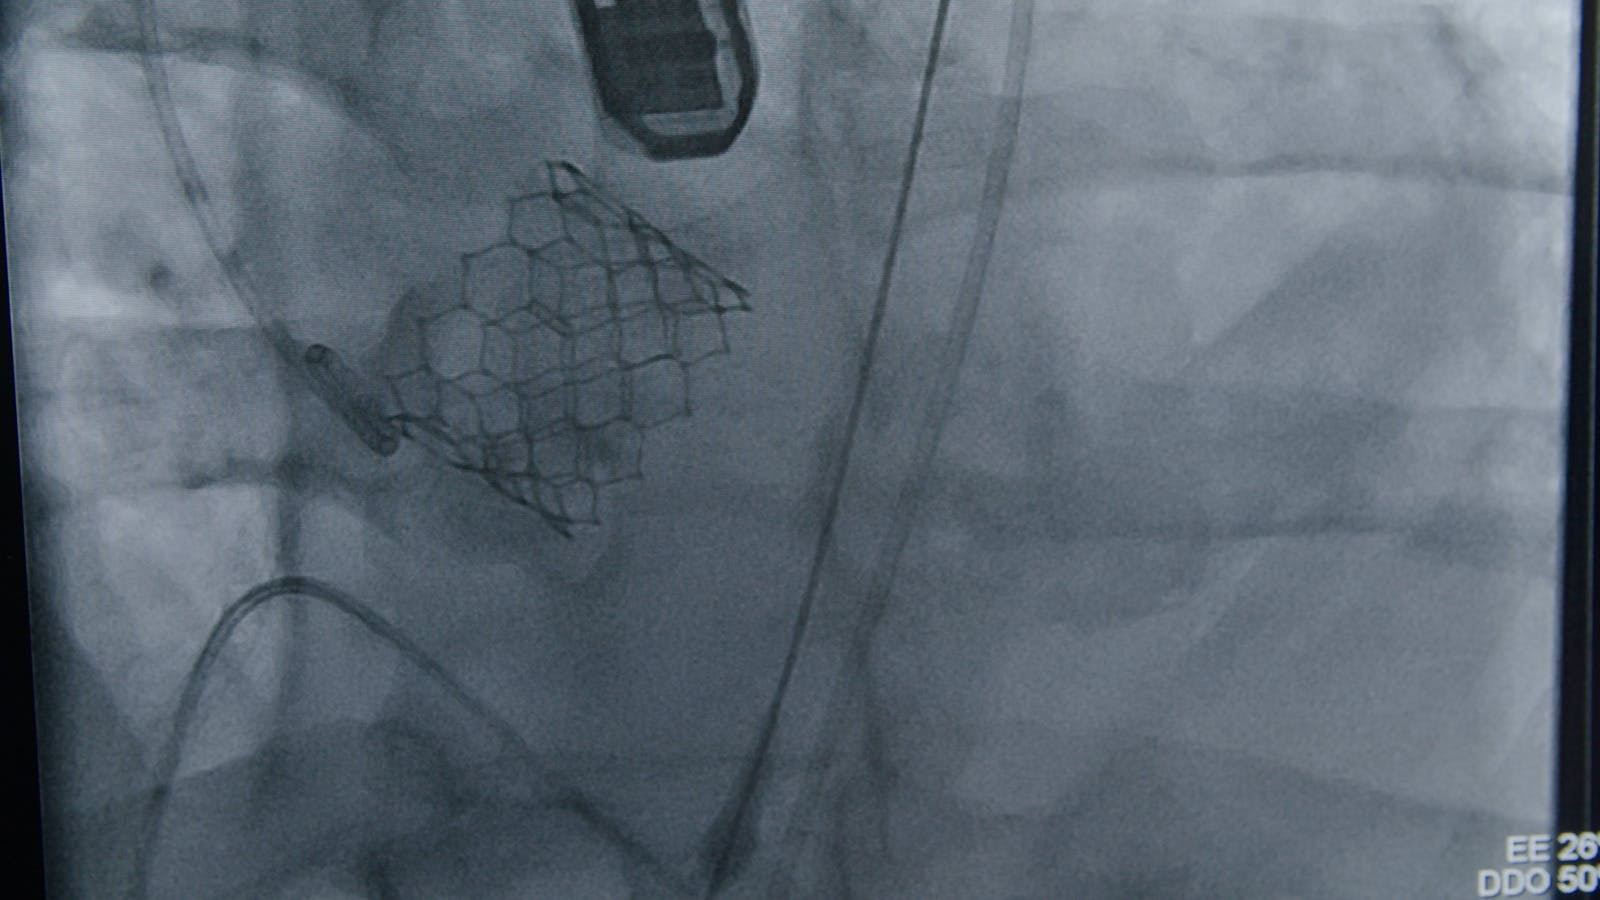

Pentru acest pacient tânăr, opțiunile erau puține. Din cauza tratamentului cu cortizon și a multiplelor comorbidități, o intervenție chirurgicală pentru înlocuirea valvei aortice era extrem de riscantă. Din fericire, inovația permite astăzi ca pacienților cu risc operator mare să le fie implantată o proteză de valvă aortică direct prin intermediul vaselor de sânge, fără să fie nevoie de operație. Deși procedura TAVI se face în general la pacienții în vârstă, cazul pacientului nostru a fost discutat în cadrul unei echipe multidisciplinare Heart Team și decizia a fost că o astfel de intervenție îi poate salva inima.

În urmă cu o săptămână, pacientului i-au fost dilatate arterele îngustate, în cadrul unei angioplastii cu balon și stent, efectuată de dr. Florin Matei.

Ulterior, echipa formată din dr. Dan Deleanu, dr. Lucian Dorobanțu, dr. Iulian Călin, dr. Irina Macovei Dorobanțu și dr. Veronica Soare a intrat în sala de angiografie cu pacientul pentru procedura TAVI. Totul a decurs conform planului, iar pacientul nostru se simte bine, se află acum în rezervă și așteaptă externarea.